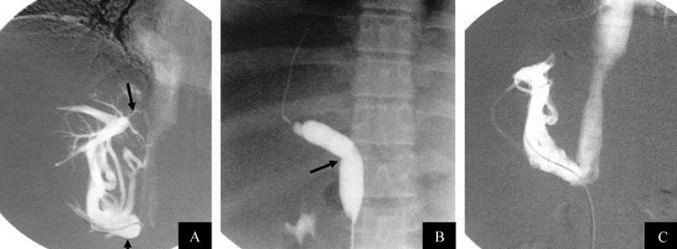

2.血管内支架置入术 血管内支架又称支撑器,是采用特殊的合金制成不同结构的圆筒形,支撑于血管狭窄病变处,使之保持血流通畅(图21-21,图21-22)。目前常用支架有热记忆合金支架、自膨式支架、球囊膨胀支架。

图21-21 血管内支架置入术示意

图21-22 Budd-Chiari综合征下腔静脉内支架置入术

A.下腔静脉造影示下腔静脉完全闭塞;B.刺破下腔静脉隔膜;C.支架置入后开通血流